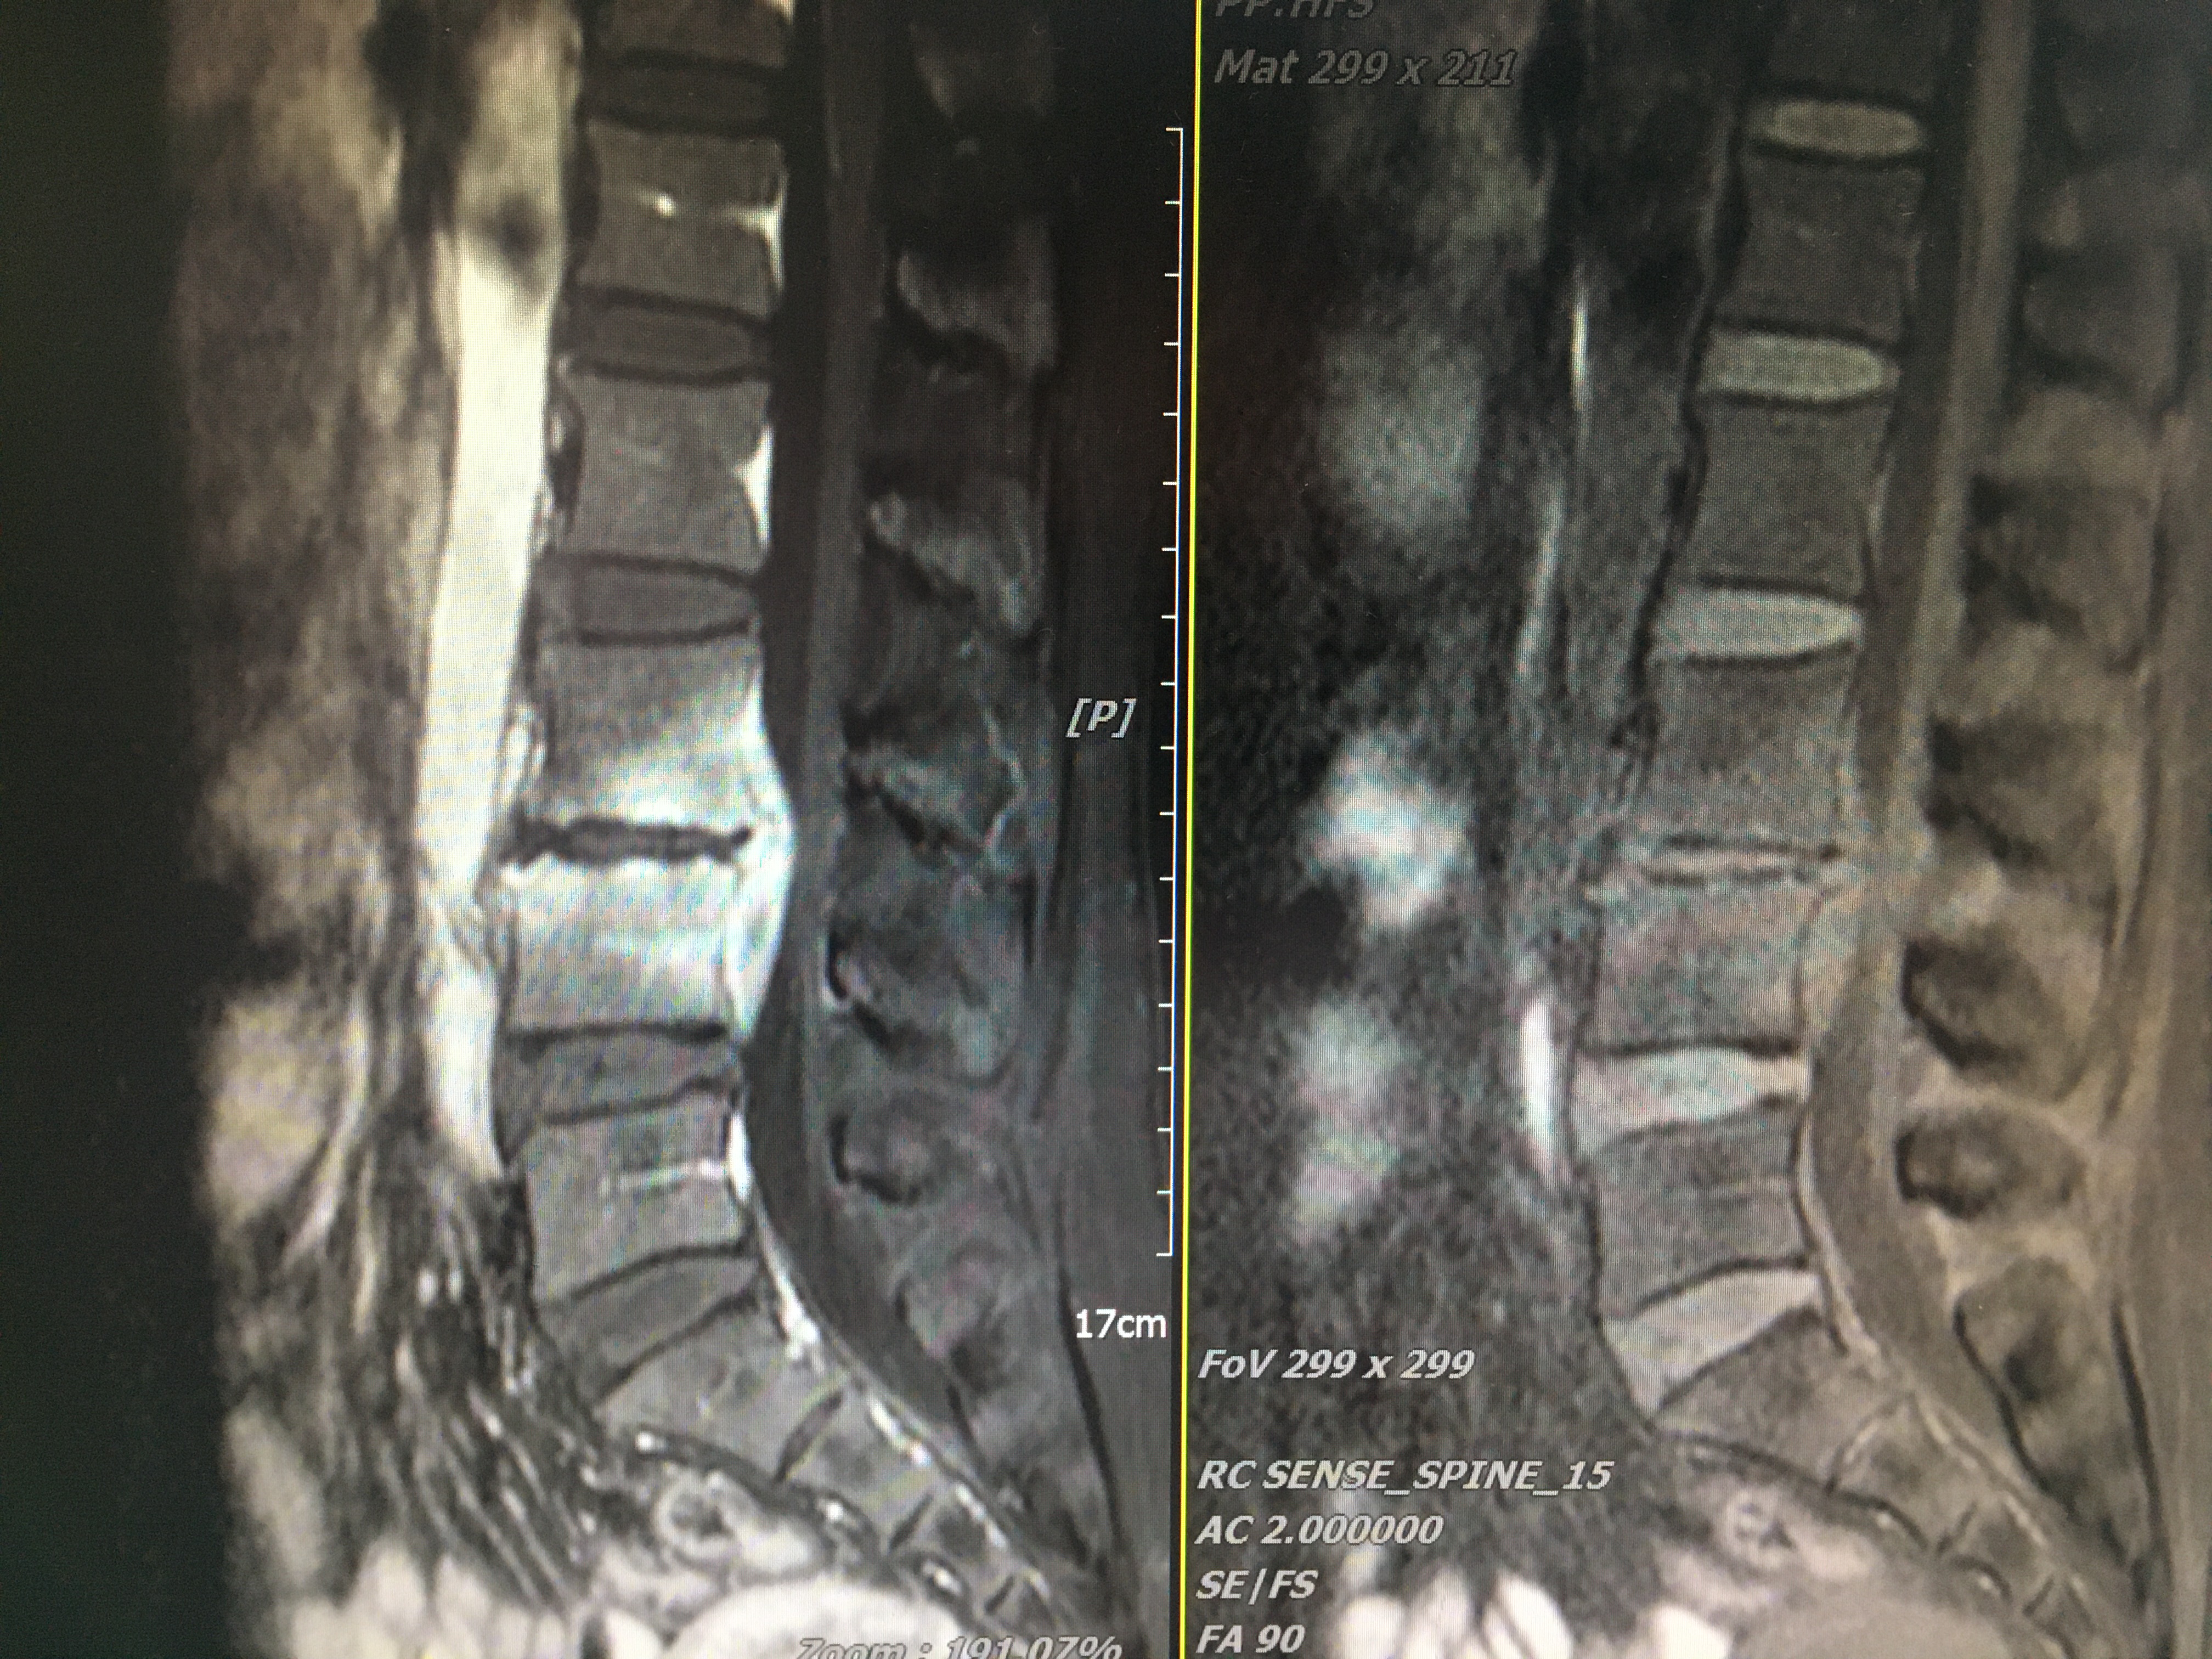

术前MRI

脊柱感染椎管内脓肿,传统手术采用后路减压+后路置钉。缺点:手术创伤较大、病灶清除相对不彻底、植骨面积小、存在脓液向椎骨内扩散等风险。经科室疑难病例讨论后,一致同意采用:经斜外侧入路(Olif入路)微创腰3-4病灶清除+取同侧髂骨椎间植骨+后路天玑机器人导航下经皮微创腰3-4椎弓根钉系统内固定术。手术在陈志伸、李毅嵩专家团队及麻醉、护理、机器人操控团队紧密配合下顺利完成,术中出血量约150ml。